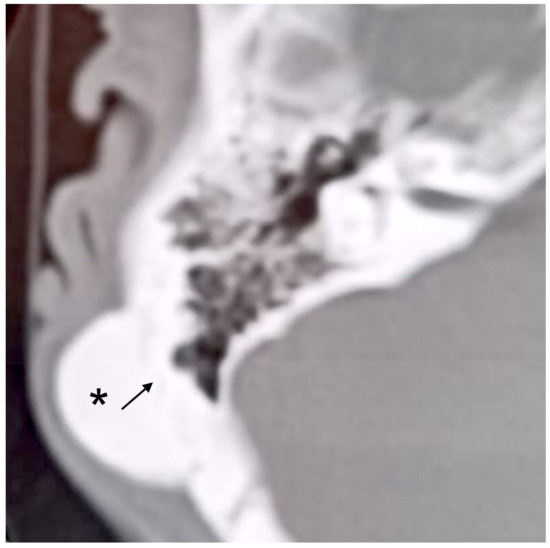

3.3. Case 3